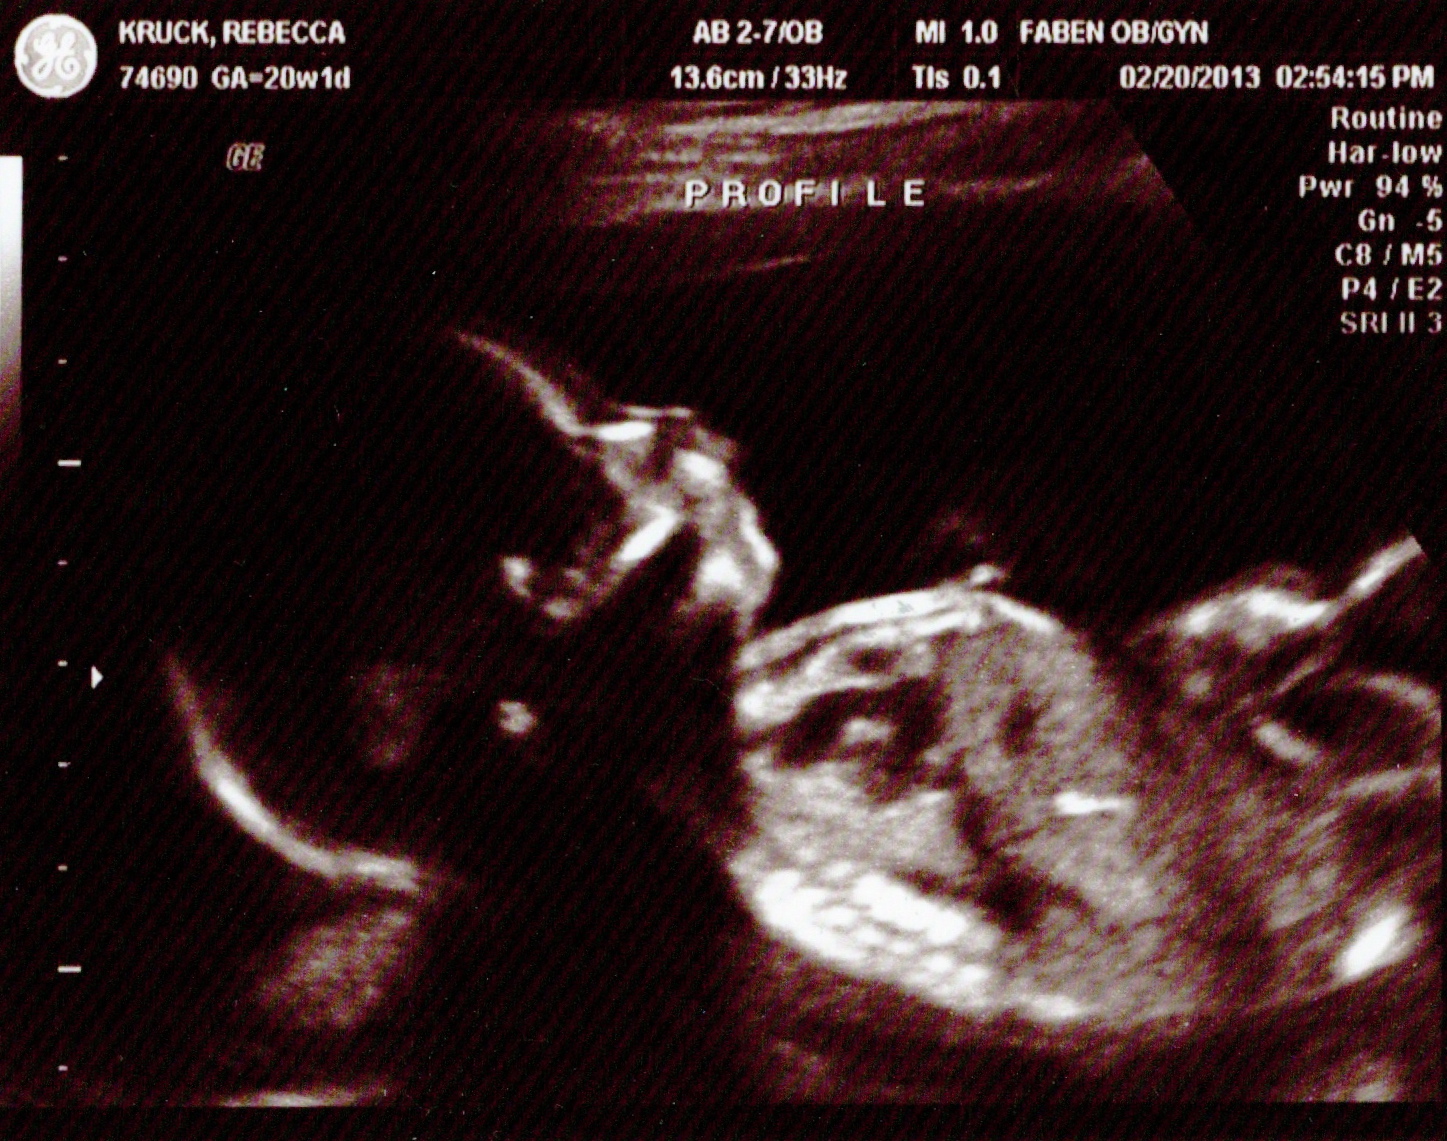

After the initial shock had worn off, we got on with our lives and the process of preparing for a baby. In the beginning, testing for the more well-known chromosomal conditions such as Down’s, DiGeorge and Trisomy 13 and 18 were negative. Our hopes began to soar, for even though we new he’d still have to have at least one surgery to repair his cleft lip/palate as well as continuous monitoring for the heart defect, it seemed like he was going to be just fine.

On April 2nd, we had our next visit at the ROC. After the usual scans (ultrasounds) were complete we were led into the office of our genetic specialist Brittany. We were told that the micro-testing had finally come back and Henry had some “extra material” on the #1 chromosome, which led to the deletion of some other material. They diagnosed this as something called 1p36 deletion syndrome. We were given an information packet (http://www.rarechromo.org/information/chromosome%20%201/1p36%20deletion%20ftnw.pdf) completed by an organization called Unique. Apparently there are a number of symptoms associated with this disorder (including cleft lip/palate and heart defects), but most commonly moderate to severe developmental delays and learning disorders.